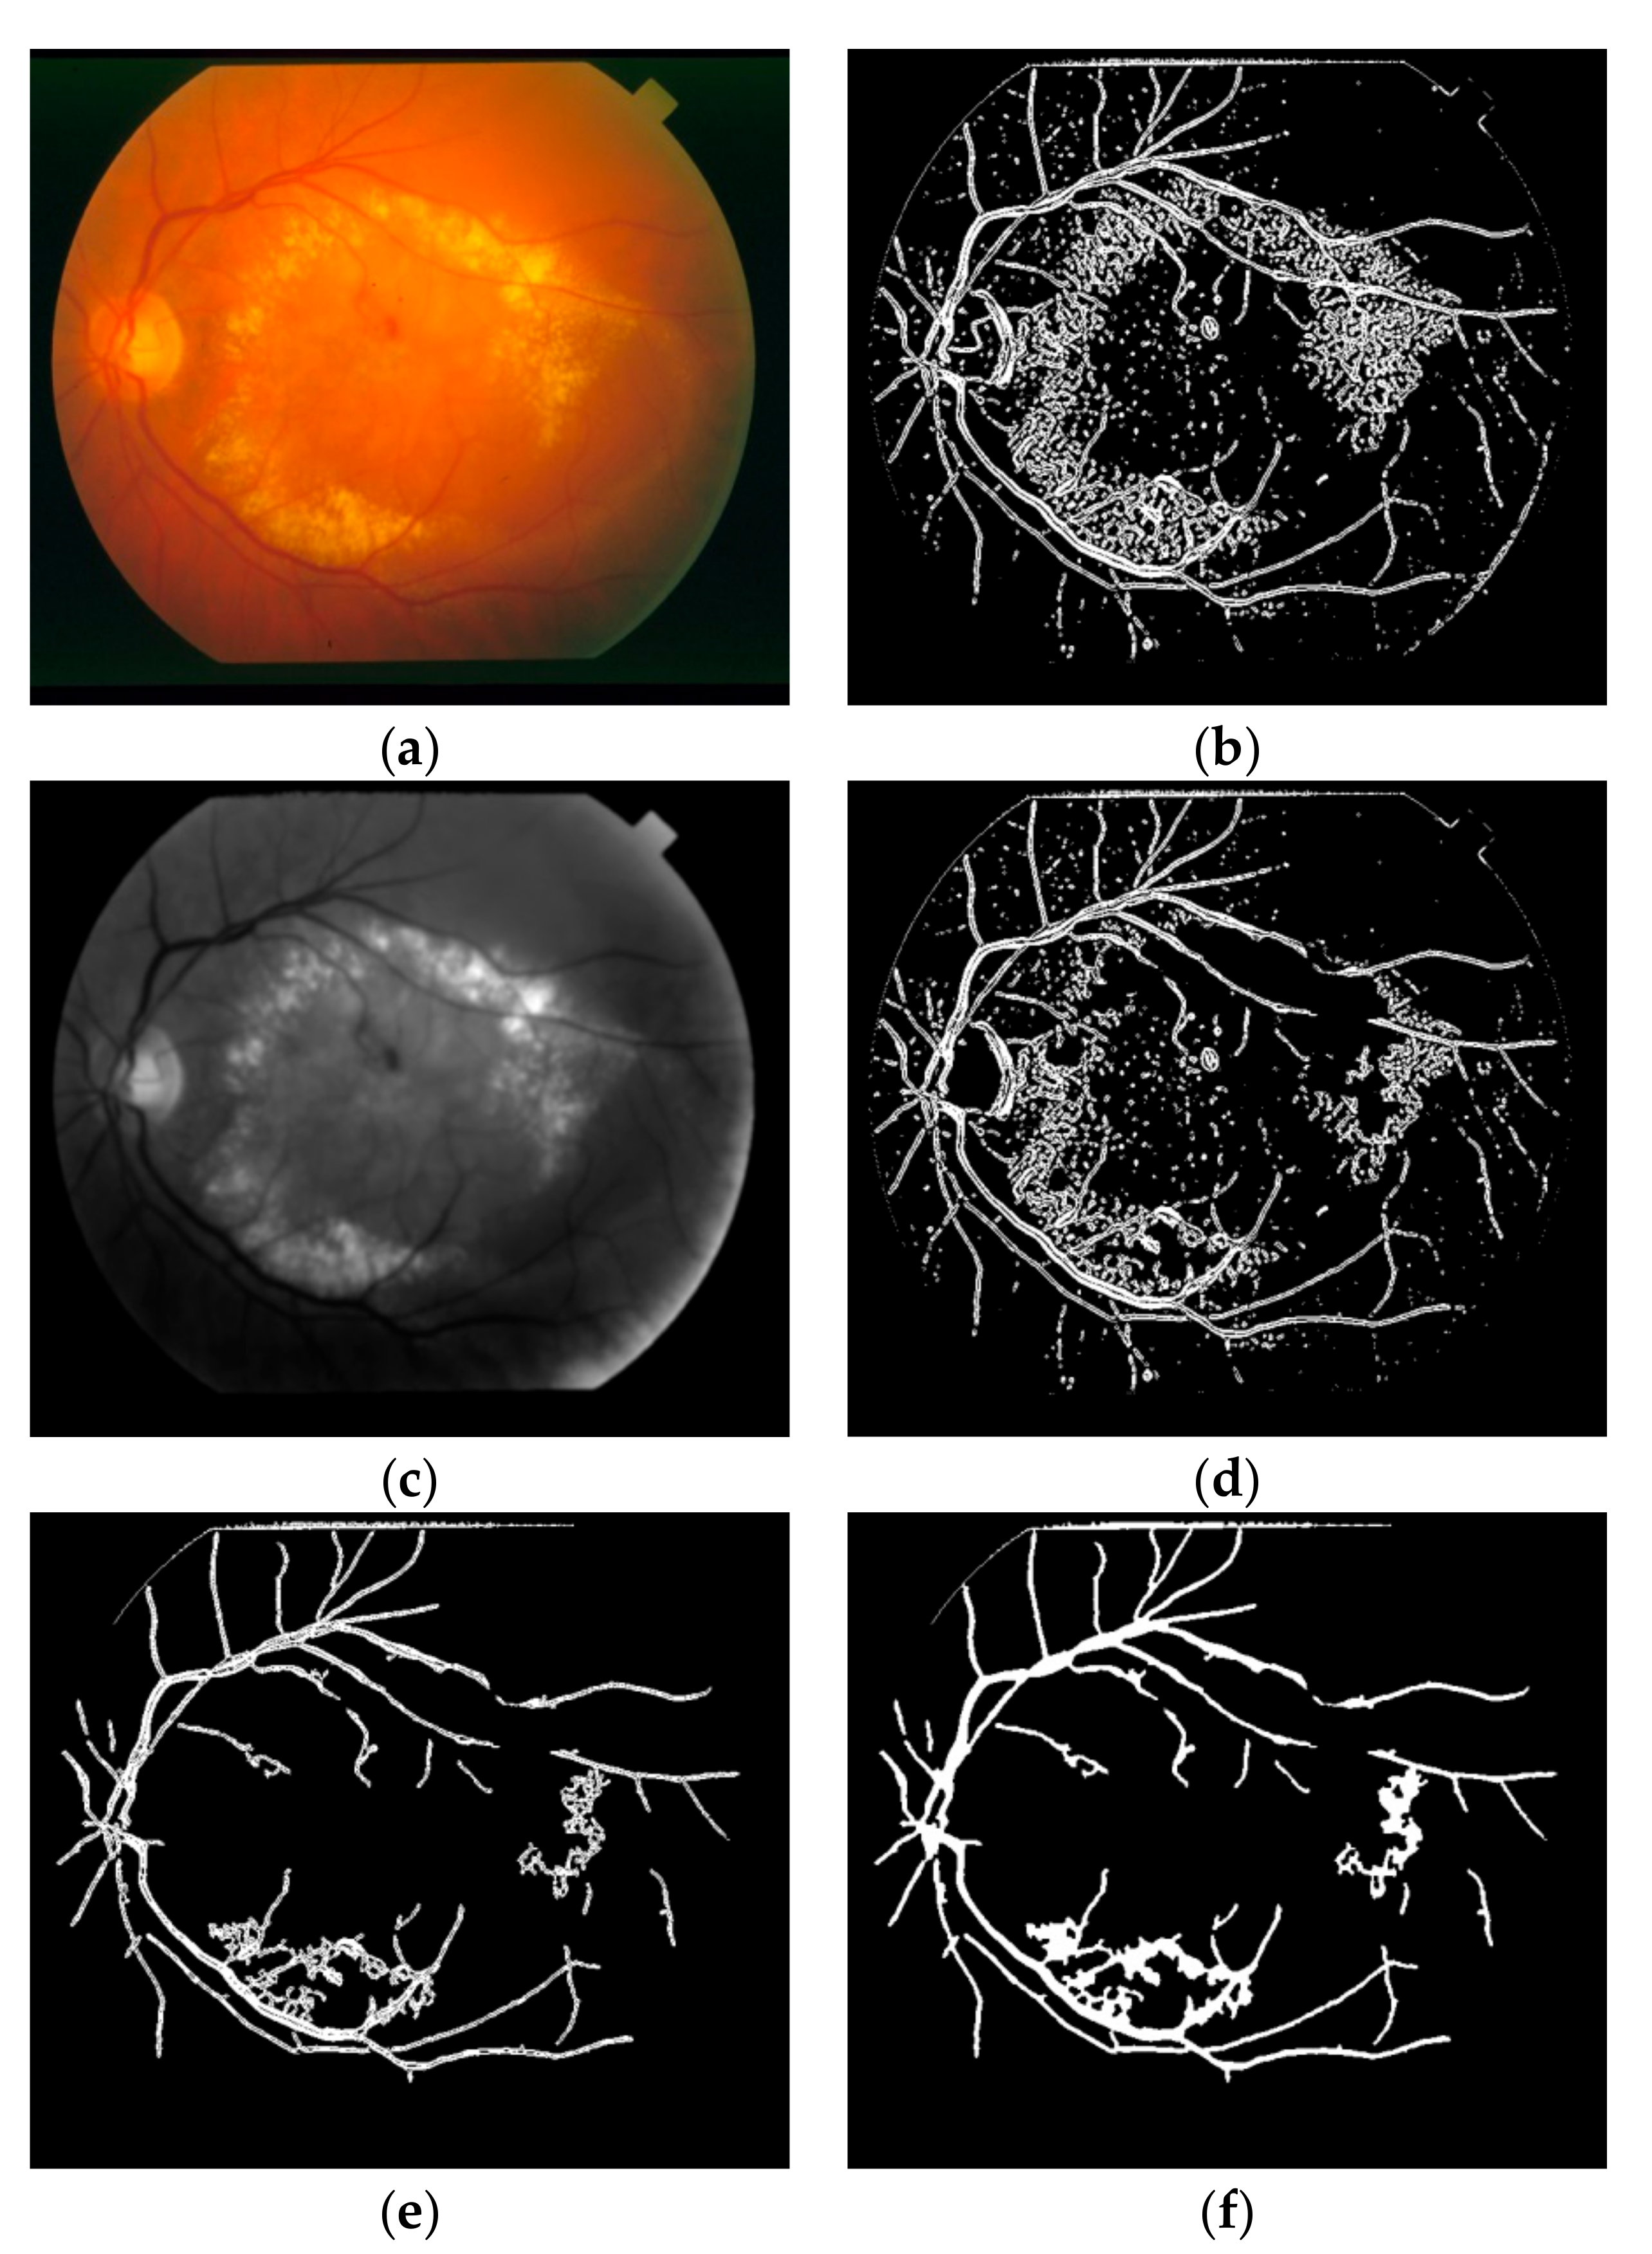

In this study, two different approaches are offered for the lesion removal procedure at the post-processing step. The effects of the post-processing procedures are shown on the segmentation steps of an image having DR in STARE dataset as in Figure 6. The first approach targets especially the spread hard and soft exudate lesions. The highest 10% of the histogram of the product of hue and green color space of the retinal image having these kinds of lesions is removed from the segmentation result as in Figure 6d.

Figure 6.

Post-processing procedures on image 2 on STARE dataset (a) retinal image having DR; (b) first segmentation result; (c) product of hue and green colors; (d) effect of histogram-based bright lesion removal step; (e) effect of solidity and eccentricity-based lesion removal step; (f) effect of small hole filling step.

The second approach aims to remove all the other lesions or residual artefacts by taking into account their geometric structures such as solidity and eccentricity. The ratio of the region of a connected component to its convex hull is defined as solidity. The ratio of the distance between the foci of the ellipse which has same the second-moments as a connected component and its major axis length is defined as eccentricity [44]. It was empirically inspected with a high probability that the connected components having solidity value above 0.3 and eccentricity value below 0.95 are lesion. After removing the lesion-like connected components as in Figure 6e, all the residual connected components which are smaller than 100 pixels are deleted from the segmentation result. Finally, the small holes occurring on the vessels because of the central vessel reflex are filled using some successive morphological operations as shown in Figure 6f.